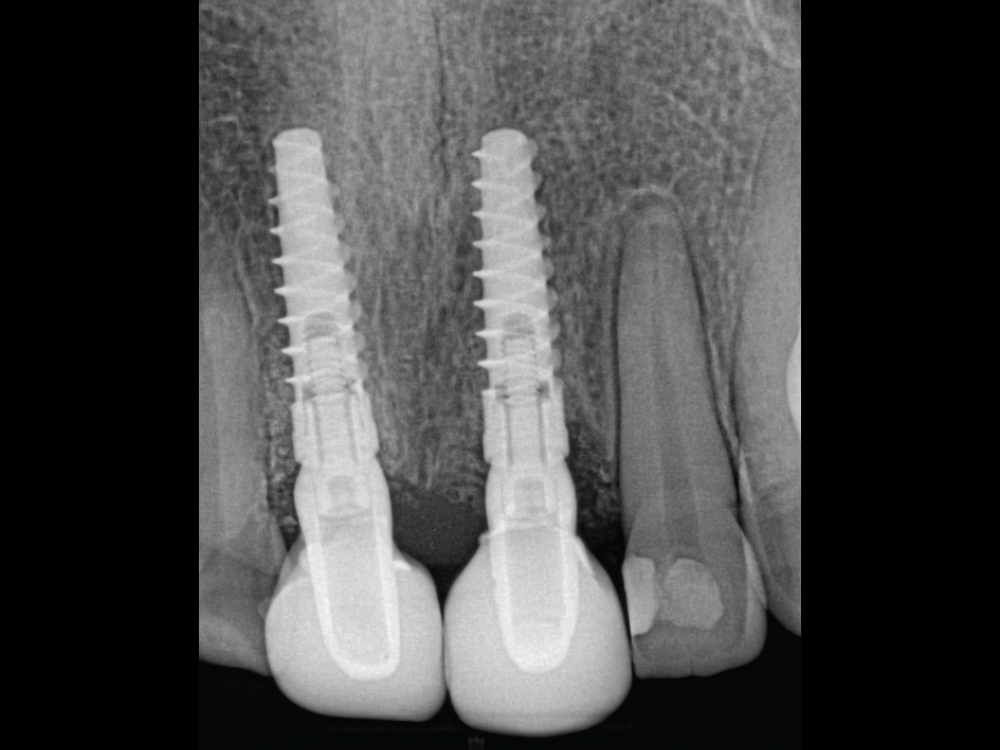

After taking care to atraumatically remove the central incisors while avoiding damage to the buccal plate, two 3.5-mm-diameter Hahn Tapered Implants were placed into the extraction sockets. The pronounced thread design of the implants helped maintain proper position against the palatal wall during placement. The gaps between the implants and the extraction sockets were filled with Newport Biologics™ Mineralized Cortico/Cancellous Allograft Blend (Glidewell Direct).

The Hahn implants achieved high primary stability, allowing for immediate provisionalization. Temporary screw-retained crowns were fabricated chairside and connected to the implants, providing the patient with fixed “teeth in a day” that would help facilitate an esthetic outcome by sculpting the gingival tissue during healing.

Scanner view of abutments

Four months after the surgical procedure, gold-tone custom abutments and all-ceramic crowns were delivered. The custom abutments and implant crowns were produced for a reduced fee because of the 20% discount offered by Glidewell for restorations over Hahn implants. The final restorations achieved esthetic, lifelike emergence profiles due to the soft-tissue management provided by the immediate provisional restorations during the healing phase. Note the crestal bone levels around the Hahn implants.